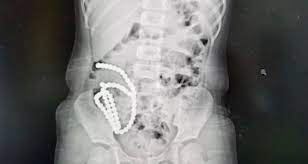

This case of marble coming out of the girl's stomach is from a city in China. The age of this girl is 4 years. The girl had swallowed about 61 small marbles. This little girl of 4 years swallowed about 61 marbles one by one. After swallowing the marbles, the girl started having a stomach ache. This girl had pain in her stomach for almost months. At last, after the report of the doctors, the secret of her abdominal pain was revealed. All the marbles had gathered together in the stomach of this girl. It can be seen in the X-ray that all the marble has gathered in its stomach like a string of pearls.

Doctors removed 61 marbles from the stomach after surgery